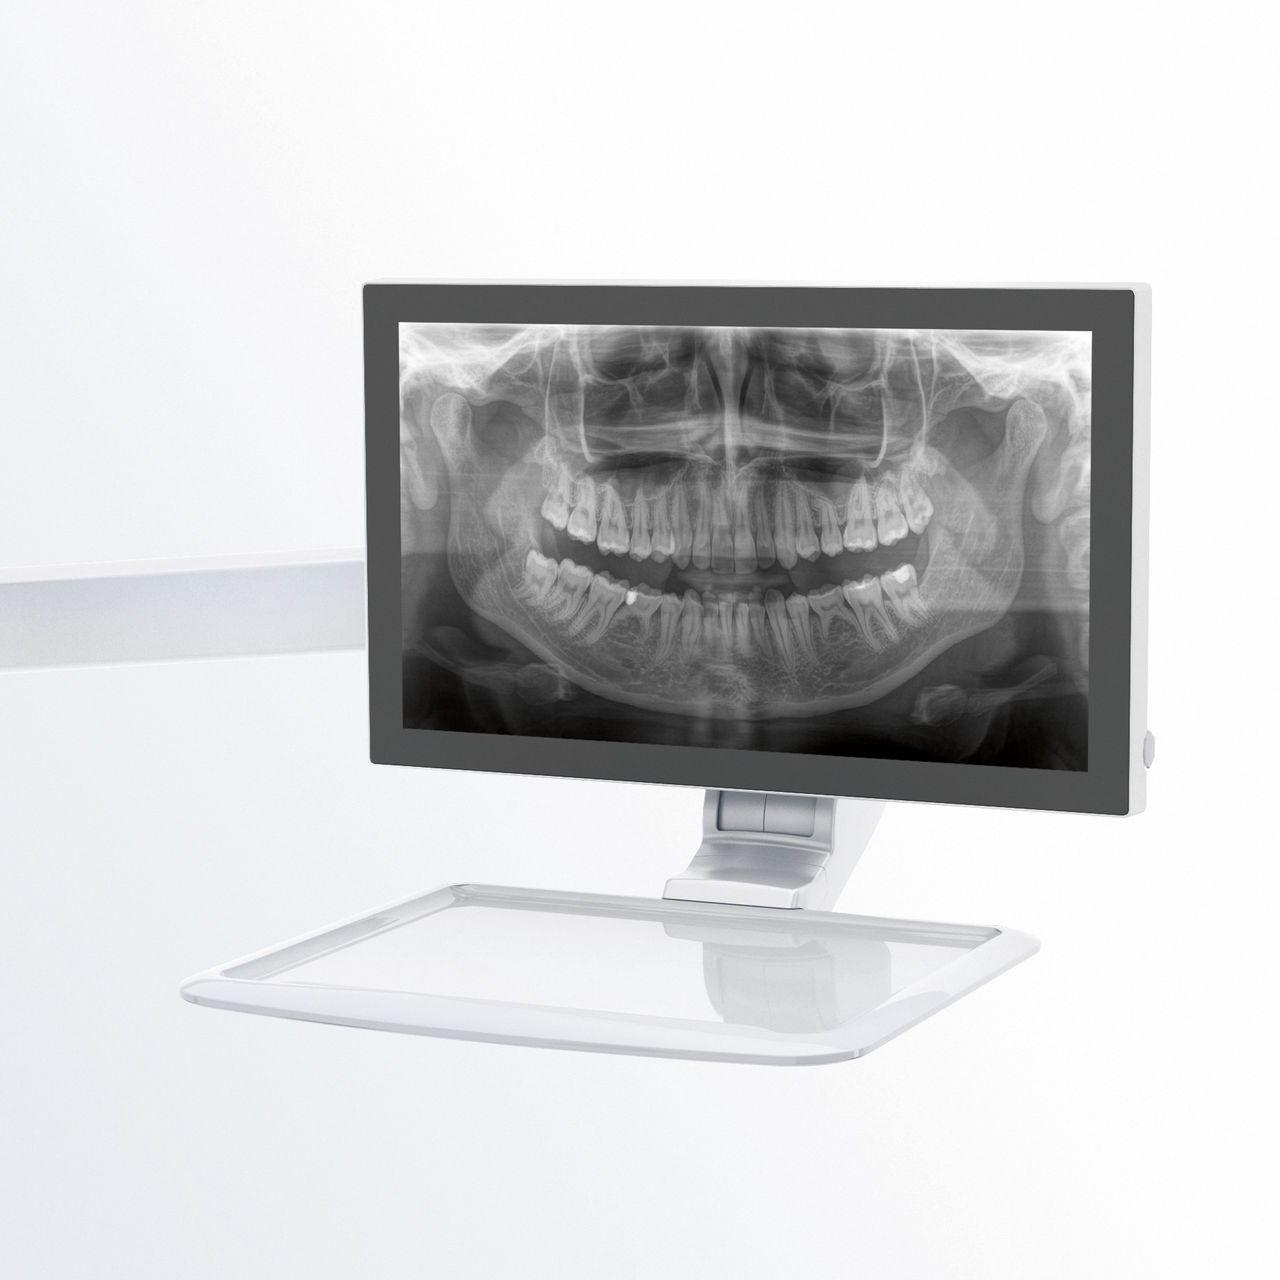

Ein entspanntes und angenehmes Vorgehen ist für alle gleichermaßen wichtig, für die Patienten wie für das Personal. Es ist zufriedenstellend und motivierend, wenn alles nach Plan läuft und die Dinge reibungslos funktionieren. Die Verwendung von Orthophos oder Axeos mit Sidexis 4 bietet Ihnen gezielte Unterstützung. Die Röntgensysteme sind einfach zu bedienen, aber einzigartig in ihren Diagnosemöglichkeiten. Dadurch wird sichergestellt, dass jeder Aspekt des Behandlungsprozesses eine positive Erfahrung darstellt.

Erfahren Sie mehr über die Röntgenlösungen von Dentsply Sirona und fordern Sie Informationen zu intraoralem Röntgen, Software oder 2D- und 3D-Bildgebungstechnologie an.